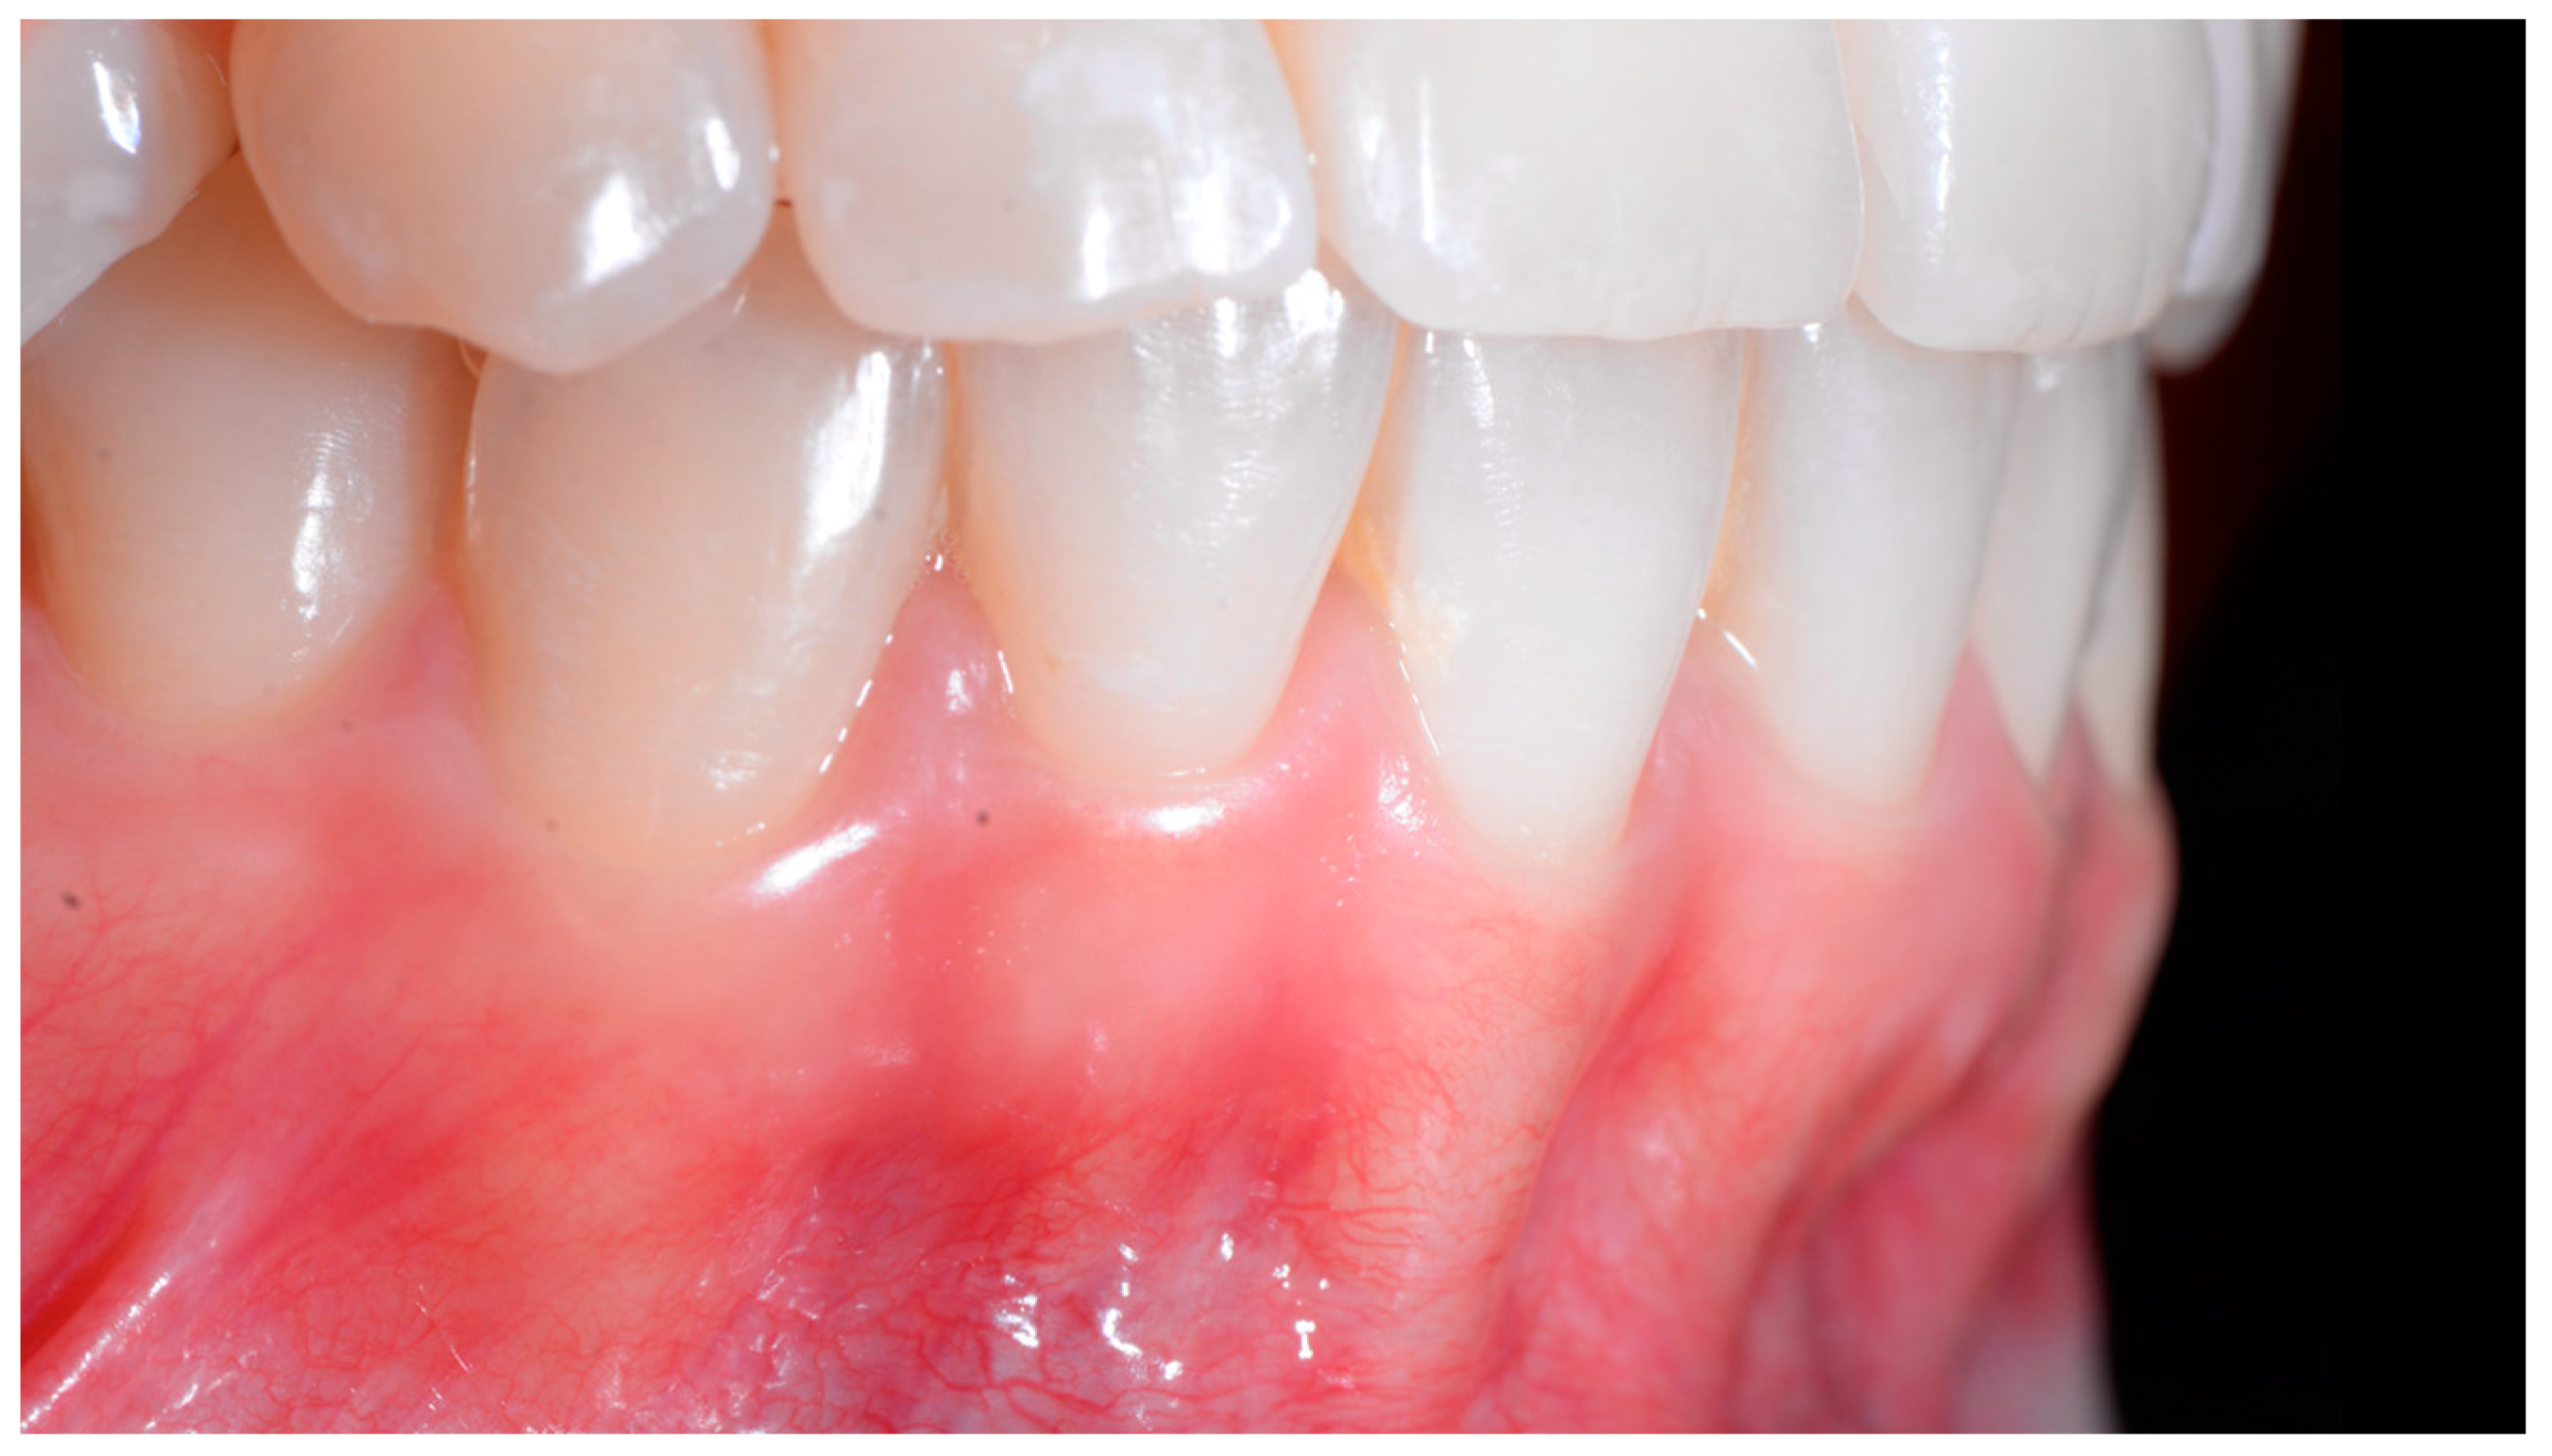

In the lateral view (Figure 3), the prominence of the root of 41 was confirmed.

Early wire syndrome. Lateral view.

The root of tooth 21 is visible through the gingiva (Figure 7). Figure 8 shows the extent of gingival recession on tooth 41.

Intermediate wire syndrome. Lateral view.

Intermediate wire syndrome. Lateral views.